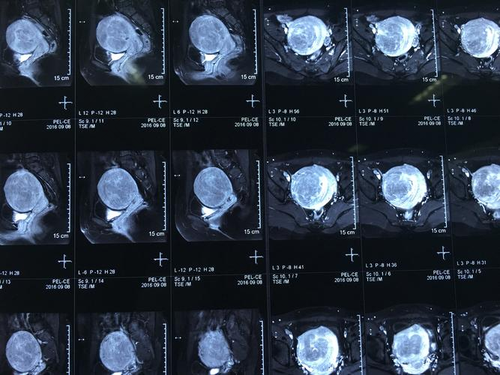

瘢痕子宫不一定要做核磁,如果瘢痕子宫的女性胎盘位于前壁,这种情况不一定需要做核磁,胎盘前壁是正常的胎盘,不会出现胎盘植入,因此不需要做核磁。但是如果胎盘位于前壁,同时合并胎盘前置,就有可能出现胎盘植入。这时候就需要做核磁,以便对局部的胎盘与肌层之间的关系进行评估。

瘢痕妊娠指的是曾经做过剖腹产的女性,再次怀孕时,孕囊刚好着床在剖腹产遗留的疤痕处的异常妊娠。这种情况常导致生产时大出血甚至子宫破裂,病情较为凶险,因此很多瘢痕子宫再次妊娠就会选择剖腹产,不过如果身体条件允许的话,也是可以做顺产的。